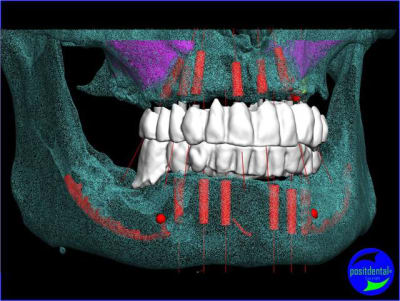

projet implantaire pour février

1er étape le wax-Up, dans ce cas clinique il est réalisé en 3D

Cette vidéo présente une gestion de l'esthétique dans un cas d'extraction, implantation, mise en charge immédiate alors qu’il ne reste pas de chicot mais des dents mobiles.

> 2 ANS après MCI Bimaxillaire en 1 intervantion

Depuis + de 10 ans Positdental a développé des solutions technique pour indexer le pilier prothétiques lorsque l'implant est angulé, une des réalisations en 2008.